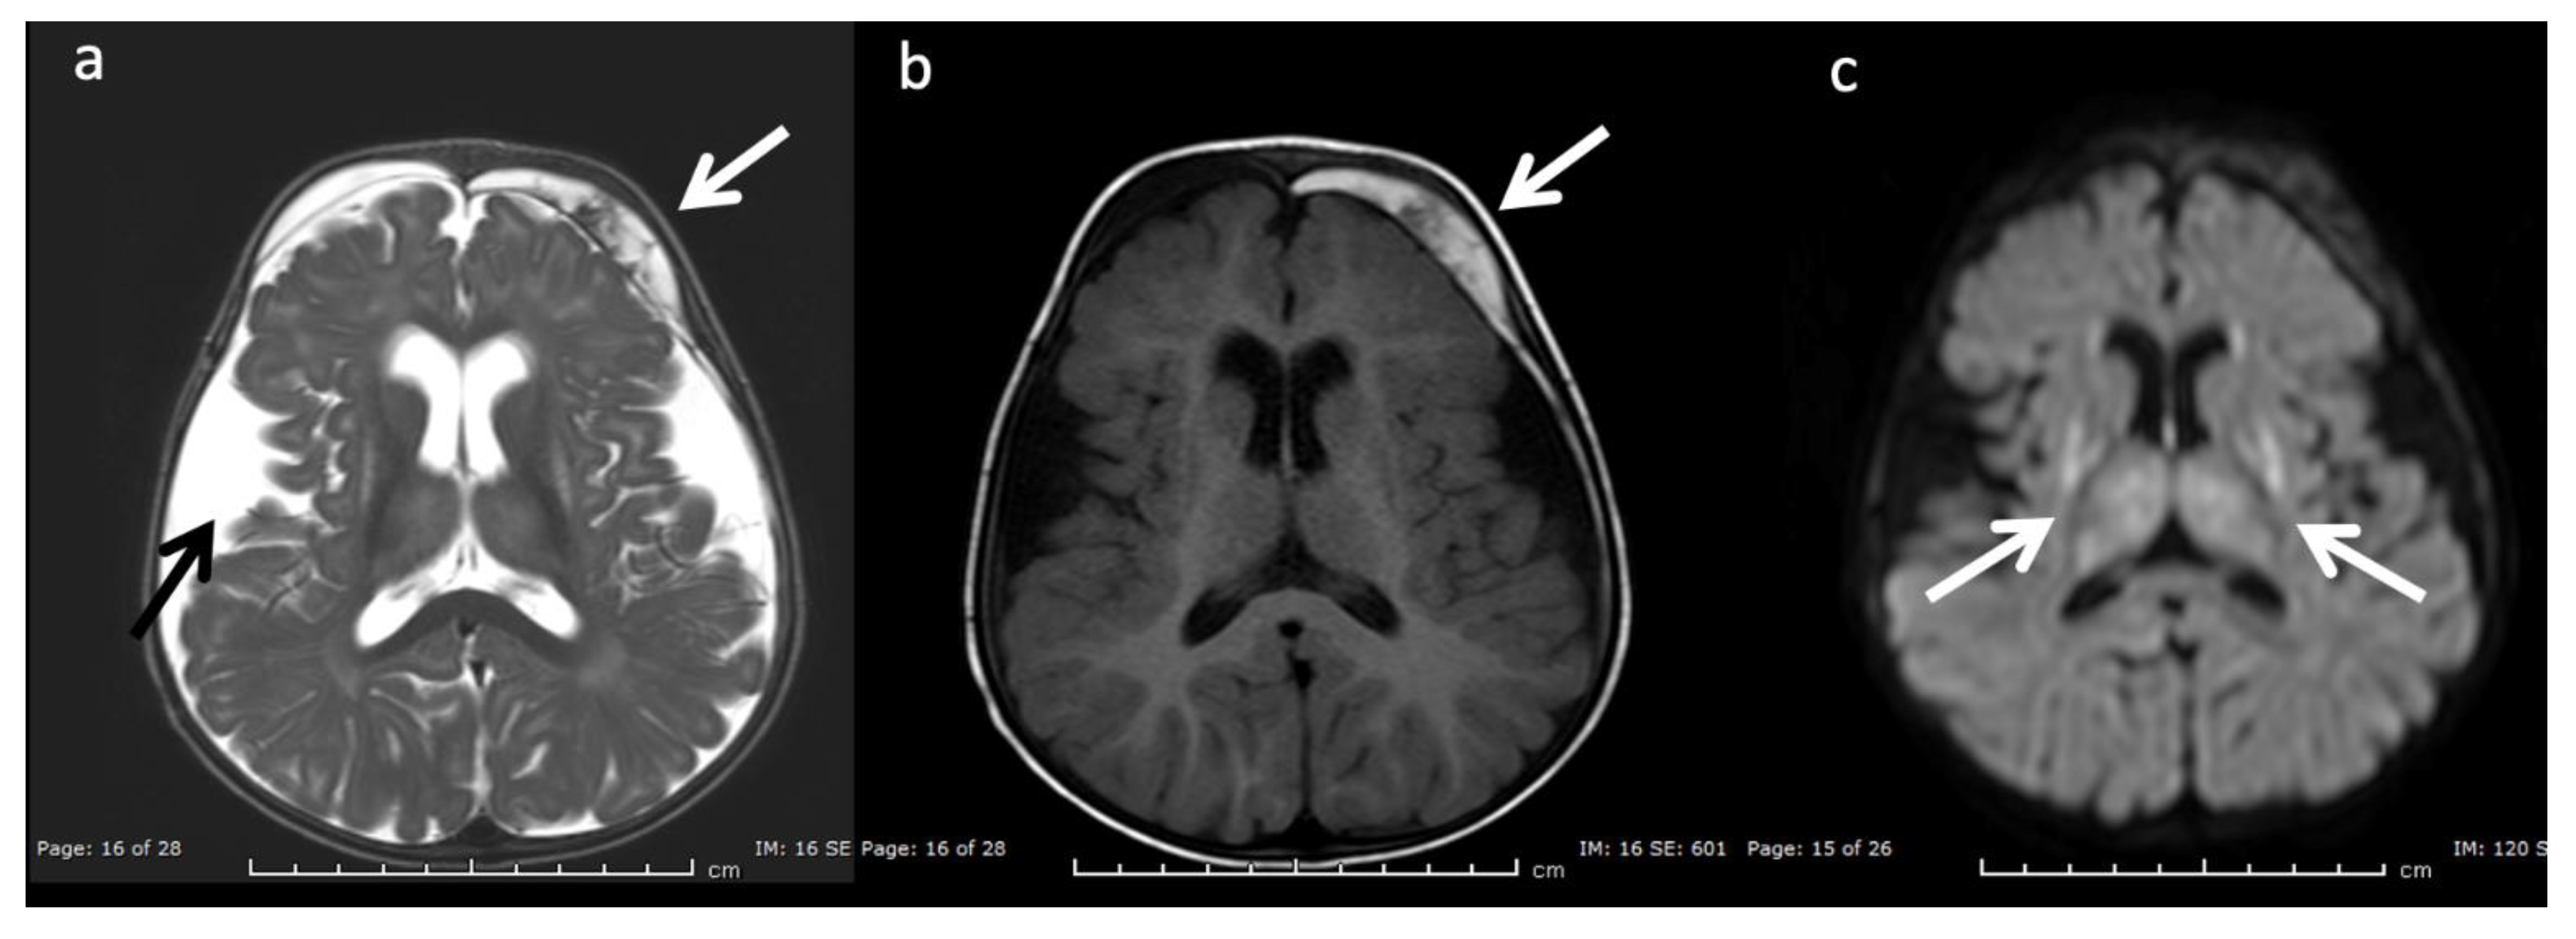

Glutaric Aciduria Type 1 (GA-I) (Figure 10): GA-I is a disorder of lysine, hydroxylysine, and tryptophan catabolism that results in characteristic MRI findings of poorly formed operculum, widened Sylvian fissures and frontotemporal CSF spaces, large cavum septi pellucidi, and basal ganglia lesions [3,7,8]. Supratentorial subdural hematomas may develop over time as a consequence of cerebral atrophy [20,36]. GA-I should be distinguished from glutaric aciduria type II that is caused by the inability to breakdown proteins and fats for energy and may present with underdeveloped frontotemporal lobes and enlarged sylvian fissures, delayed myelination, and hypoplasia of the corpus callosum [37].

Figure 10.

Eleven-month-old female with Glutaric aciduria Type I with acute decompensation after illness. (a) Axial T2WI, (b) T1WI, and (c) DWI at the level of the basal ganglia demonstrate diffuse cerebral volume loss, underopercularization (black arrow, a), bifrontal chronic subdural hemorrhages with superimposed subacute left frontal subdural blood products (white arrows, a and b), and reduced diffusion in the lentiform nuclei and thalami (white arrows, c).